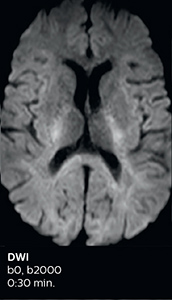

This is an example of acute ischemic stroke with distal occlusion of the right posterior cerebral artery. Note the improved visibility of the ischemic territory on the diffusion weighted image with high b-value. The 3D FLAIR shows a distal PCA occlusion. The fast SWIp depicts the thrombus on the isolated second echo image. The total scan time (including SmartBrain, preparations and a fast 3D T1w TSE Gd) is 8:00 minutes.